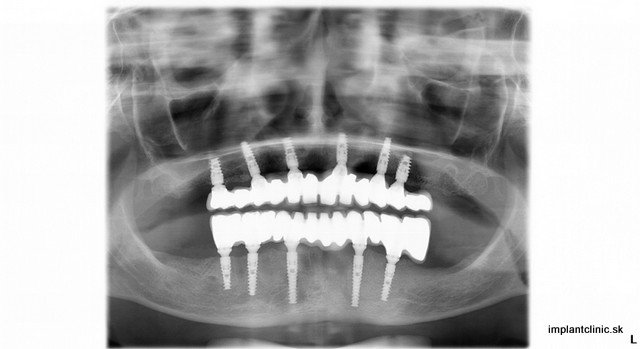

Už sa nemusíte trápiť so snímateľnou protézou. Vymeňte svoju snímateľnú protézu za fixnú. Existuje spôsob náhrady všetkých zubov, ktorý vám pomôže zabezpečiť plnohodnotný, pohodlný život bez trápnych situácií, ktoré vám môže vyberateľná protéza priniesť. Veľa pacientov si chváli fixné protézy nasadené na zubných implantátoch. Výhoda týchto náhrad nespočíva len v pohodlnosti, ale aj vo funkčnosti. Implantáty pomáhajú pri zachovaní kosti, hryzenie a žutie je pohodlnejšie a jednoduchšie. V neposlednom rade veľkou výhodou je trvácnosť implantátov. V mnohých prípadoch vydržia aj doživotne.

Iveta bola veľmi spokojná s prácou nášho implantologického tímu a zubných technikov, ktorí odviedli vynikajúcu prácu. Korunky sú vyrobené z vysokokvalitnej keramiky a jadro implantovej korunky je vyrobené z titánu. Zubné implantáty Ankylos používané v Implantclinic sú vyrábané z veľmi odolného kvalitného titánu. Je to kov bežne používaný v zdravotníctve. Je biokompatibilný a dlhodobo odskúšaný.

Implantová protéza sa upevní na 4 – 5 implantátoch na ktorých drží fixne. Aj o Vašu protézu sa musíte strať ako o vlastné zuby. Vyžaduje si to ale dôkladnejšie čistenie v ťažko dostupných miestach, aby sa predišlo nahromadeniu povlaku v okolí implantátov. Váš hygienik Vám ukáže, ako sa správne starať o Vašu zubnú náhradu a aké pomôcky používať.